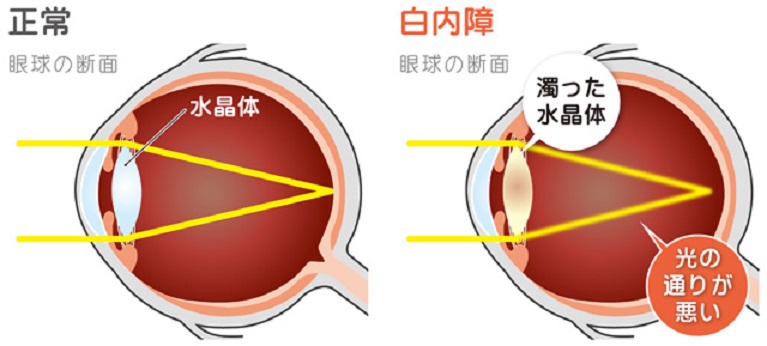

白内障

主に加齢を原因として、水晶体が濁る病気です。年齢を重ねるごとに発症率は高くなり、80歳以上の方のほぼ100%に見られます。一方で、40代で発症することもあります。目のかすみ、物が二重・三重に見えるといった症状に加えて、まぶしさを伴うことがあります。

主に加齢を原因として、水晶体が濁る病気です。年齢を重ねるごとに発症率は高くなり、80歳以上の方のほぼ100%に見られます。一方で、40代で発症することもあります。目のかすみ、物が二重・三重に見えるといった症状に加えて、まぶしさを伴うことがあります。